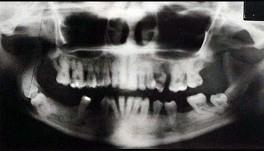

问题 关于快速进展性牙周炎,哪项正确 ( )

选项 A.发病年龄青春期至25岁之间 B.病损好发于第一恒磨牙和上下前牙 C.有严重及快速的骨破坏,然后破坏过程自然停止或显著减慢 D.所有患者都有中性粒细胞及单核细胞的功能缺陷 E.本病极少伴有全身症状

答案 C